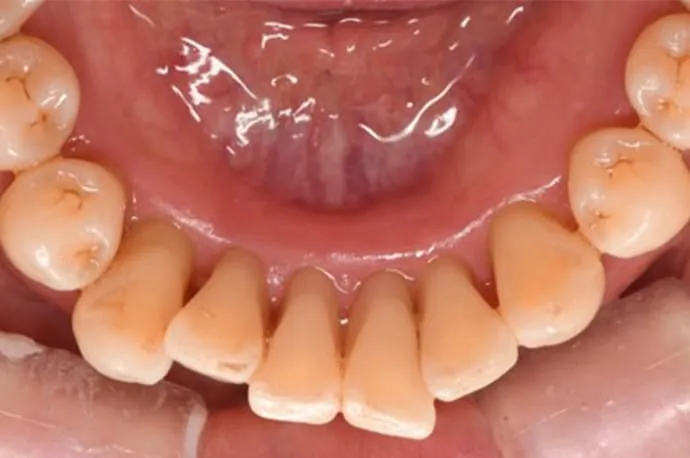

治療前

治療後

歯周基本治療後の状態です。治療により歯ぐきの腫れや出血が改善し、炎症が落ち着いている様子が確認できます。歯石の除去によって、口臭やお口の中の不快感も軽減しています。

※歯周病によって歯ぐきが腫れていた場合、炎症が治まることで歯ぐきが引き締まり、治療前より下がったように見えることがあります。

※歯石除去後、一時的に知覚過敏の症状が出る場合があります。